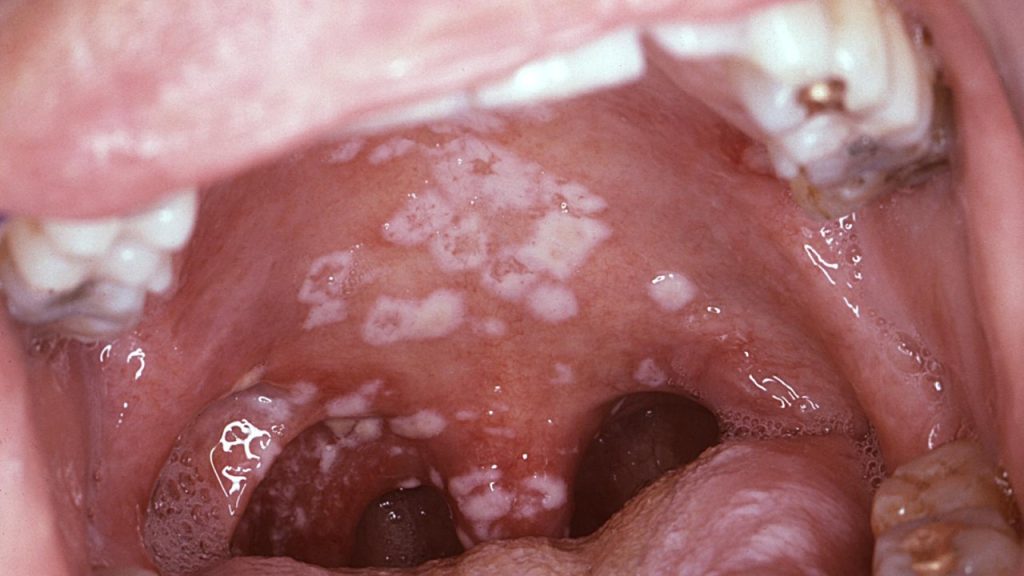

Ağız mantarı (pamukçuk), genellikle Candida albicans adlı bir mantarın neden olduğu ağız içinde beyazımsı lekeler, kızarıklık ve bazen ağrıya neden olan bir enfeksiyondur.